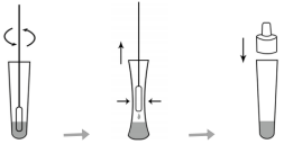

(3) Sample processing: The collected sample should be processed with the sample buffer provided by this kit as soon as possible (if it cannot be processed immediately, the sample should be stored in a dry, sterilized and sealed container) for future inspection. 2℃~8℃ should not exceed 24 hours, -70℃ should be stored for a long time (but repeated freezing and thawing should be avoided).

Figure 3 Sample processing